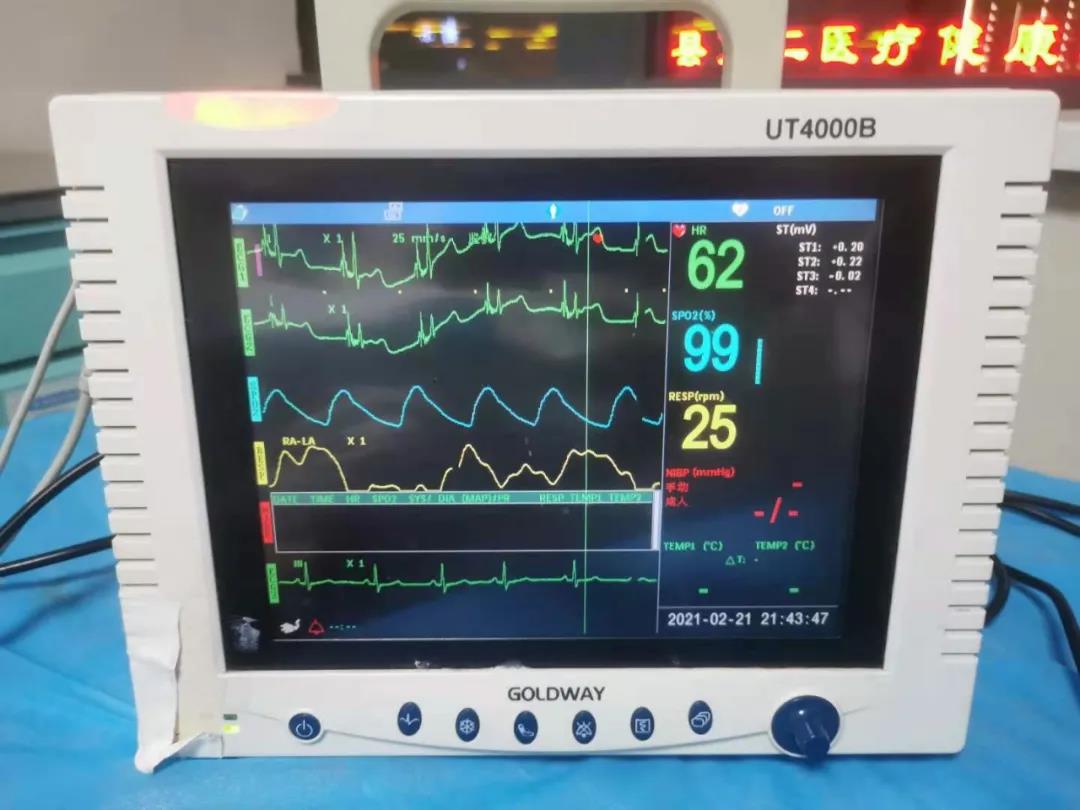

2月22日,由郸城县第二医疗健康服务集团郸城县中医院肿瘤血液科护士长刘晓娟,护士丁星文、马慧、张玉霞成立的静脉治疗专科小组,在经过了数例PICC置管中进行心电腔内(ECG)定位与x线下定位结果的比较后成功运用了ECG定位技术置管,此项技术的成功开展,标志着医院PICC置管定位技术又上新台阶!

ECG腔内定位技术是一种在置管过程将特殊的心电导联线联接导管导丝和心电图机,在送入导管过程中通过观察心电图上P波的特征性变化来判断导管尖端的位置的方法,此项技术实现了在术中实时定位和调整导管头端,达到精准定位PICC导管头端位置的目的。

ECG定位技术通过一“进”两“退”的方式(一进:当导管尖端到达CAJ时,可见高尖P波,进入右心房后P波双向,由高尖再转低;一退:当导管尖端从右心房退回上腔静脉时P波恢复正常。再退:导管继续后退2-3 cm到达最终正确的位置。)判断导管尖端位置,及时纠正导管异位、极大的提高了导管尖端位置定位的准确性,避免了因反复调整导管位置所致的并发症(静脉炎、导管相关感染、血栓等)及因导管异位而重复拍片,保证了患者安全,提高了工作效率。③7